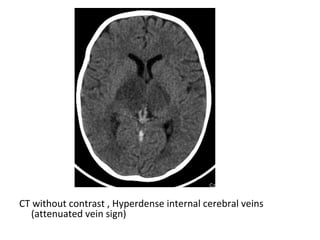

CT without contrast , Hyperdense veins (attenuated vein sign)

CT without contrast , Hyperdense internal cerebral veins

(attenuated vein sign)